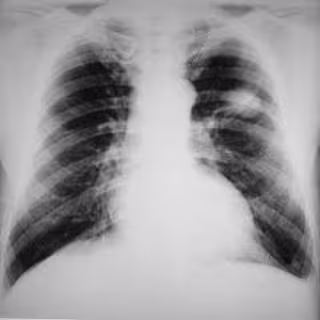

La incidencia de cáncer de pulmón en pacientes con enfermedad pulmonar obstructiva crónica (EPOC) es entre dos y tres veces superior a la de fumadores que no sufren esta enfermedad, según varios estudios encargados de analizar las causas de muerte de pacientes con EPOC en distintos estadios de la enfermedad publicados en la revista de la Sociedad Española de Neumología y Cirugía Torácica (SEPAR), 'Archivos de Bronconeumología'.

Asimismo, los estudios concluyen que el cáncer de pulmón y las enfermedades cardiovasculares constituyen las causas de muerte más frecuentes en los pacientes con enfermedad leve o moderada, mientras que la insuficiencia respiratoria es la causa más frecuente en aquellos con enfermedad avanzada. En este sentido, la neumóloga y miembro de SEPAR, la doctora Esther Barreiro, señaló que "se ha establecido a la EPOC como un factor de riesgo independiente para el desarrollo de cáncer de pulmón".

Los mecanismos por los cuales la EPOC induce un aumento del riesgo de aparición de una neoplasia "apenas se conocen", si bien se acepta que "la inflamación crónica probablemente desempeña un papel clave en la patogénesis del cáncer de pulmón en los pacientes con EPOC", apuntó la doctora. De este modo, diversas enfermedades inflamatorias crónicas en otros órganos constituyen un buen sustrato patológico para el desarrollo posterior de neoplasias relacionadas, como la pancreatitis crónica y la neoplasia de páncreas, el esófago de Barrett y el cáncer esofágico, la enfermedad inflamatoria intestinal y el cáncer de colon, entre otras, explicó esta experta.